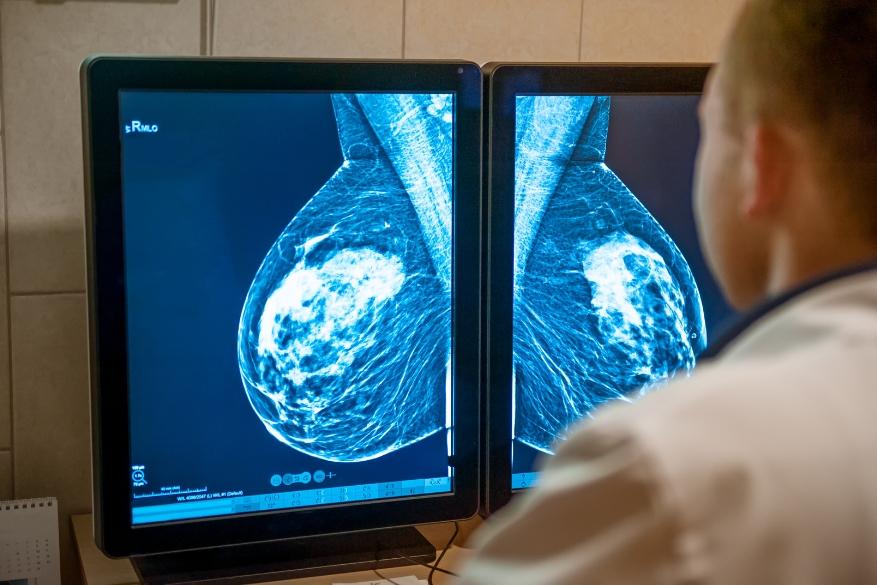

Κατά τη διάρκεια μιας δισδιάστατης μαστογραφίας (ονομάζεται επίσης συμβατική ψηφιακή μαστογραφία), λαμβάνονται δύο λήψεις από κάθε μαστό - μία λοξή (45μοιρών) και μία κεφαλοουραία (90μοιρών). Η συμπίεση του μαστού είναι απαραίτητη για τις καλύτερες εικόνες.

Με την 2D ψηφιακή μαστογραφία, ο ακτινολόγος βλέπει τους ιστούς του μαστού να επικαλύπτονται και να φαίνονται σαν μια επίπεδη εικόνα. Αυτή η επικάλυψη του αδενικού ιστού κάνει τις αλλοιώσεις δυσδιάκριτες.

Οι συμπροβολές μπορούν επίσης να δημιουργήσουν περιοχές που εμφανίζουν κάποια ανωμαλία, με αποτέλεσμα οι εξεταζόμενες να χρήζουν περαιτέρω ελέγχου με πρόσθετες εξετάσεις για να διαπιστώσουμε ότι δεν υπάρχει κακοήθεια (τα λεγόμενα ψευδώς θετικά).